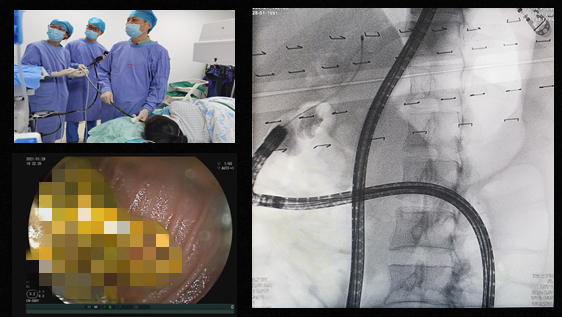

我院消化内科高度重视,详细了解患者的手术吻合方式后,经科室讨论制定了详尽的手术方案。张鸣青主任医师考虑到患者曾行胆肠及Roux-en-Y吻合术,普通内镜无法完成ERCP取石手术,需使用小肠镜进行取石。手术操作的难点在寻找输入袢及到达胆肠吻合口进行取石。曾伟副主任医师在张鸣青主任医师的指导下,使用小肠镜进镜到达R-Y吻合口,进入输入袢,寻及胆管开口,进行胆管支架取出及胆管取石。由于存在进镜路径长、确认输入袢困难、进入输入袢角度刁钻等情况,手术过程异常艰辛。

操作中首先寻找输入袢进镜,借助X线影像确保进镜方向正确,历时近2小时,拉直镜身距门齿约120cm终于见到胆肠吻合口、胆道支架残留并结石形成。使用圈套器拔除支架后,见大量结石自肝胆管排出,导丝引导鼻胆管进入肝内胆管造影,仍见多发结石透光区,反复使用取石网篮取出多块黄色结石,最后经鼻胆管冲洗胆管,见大量泥沙样结石排出。经过5个小时的努力,终于成功完成手术。术后观察2天,患者无不适,平安出院。